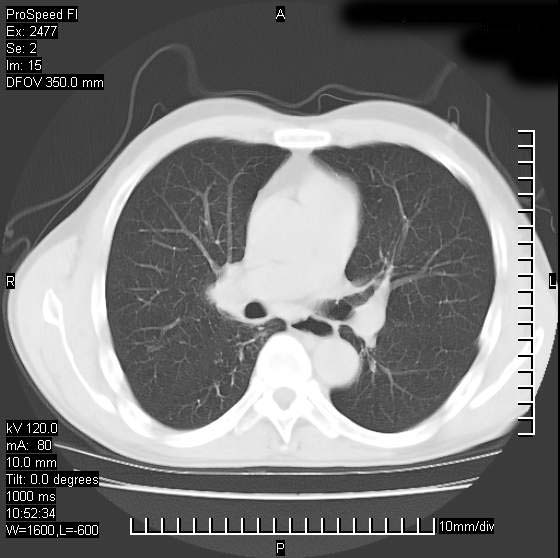

以下是引用天南地北在2007-10-9 14:29:00的发言:[br]1:右上肺结核[br]2:右肺下叶肿块:不支持肺癌,首先考虑炎性病变-肺脓疡可能性大[br]理由:1:临床病史支持,肺脓肿症状不明显应该是不规则服药造成。[br] 2:肿块边缘模糊,周围可见炎性渗出,长毛刺,内见支气管征,不过有点不规则。[br] 我感觉下肺癌这个诊断有点偏左,建议积极抗炎治疗后复查

以下是引用卜一在2007-10-9 15:55:00的发言:[br][br] [br] 1:右上肺结核[br]2:右肺下叶肿块:不支持肺癌,首先考虑炎性病变-肺脓疡可能性大[br]理由:1:临床病史支持,肺脓肿症状不明显应该是不规则服药造成。[br] 2:肿块边缘模糊,周围可见炎性渗出,长毛刺,内见空气支气管征,不过有点不规则。[br] 我感觉下肺癌这个诊断有点偏左,建议积极抗炎治疗后复查![br]支持! [br] [br] [br]

以下是引用wxy7406在2007-10-9 21:02:00的发言:[br]结合临床病史首先考虑感染性病变,但周围型肺癌不能除外,1.患者年龄偏大2.临床有咯血3.(也觉得是最重要的一点)病灶内有偏心性空洞。

以下是引用王仕学在2007-10-9 13:48:00的发言:[br]右下肺周围性肺癌可能性大,最好活检吧

以下是引用hhcckk在2007-10-9 15:18:00的发言:[br]右上肺病灶考虑结核,病灶多种形态并存(纤维化、增殖性病灶并存)[br]右下肺病灶比较难说,个人意见更趋向于“天南地北”的诊断----肺脓肿[br]1、病人有明显的寒战,高热,肿瘤病人很少出现[br]2、病灶周围的肺纹理走向柔和,没有肿瘤病灶常见的集束征[br]3、病灶边缘的毛刺较长,恶性肿瘤多为短毛刺[br]痰中血丝和病人的年龄是两个不利于良性肿块的因素,建议早点活检

以下是引用ydx_74在2007-10-9 15:53:00的发言:[br]右上肺结核,右下中心性肺癌可能大,肺门淋巴结肿大。